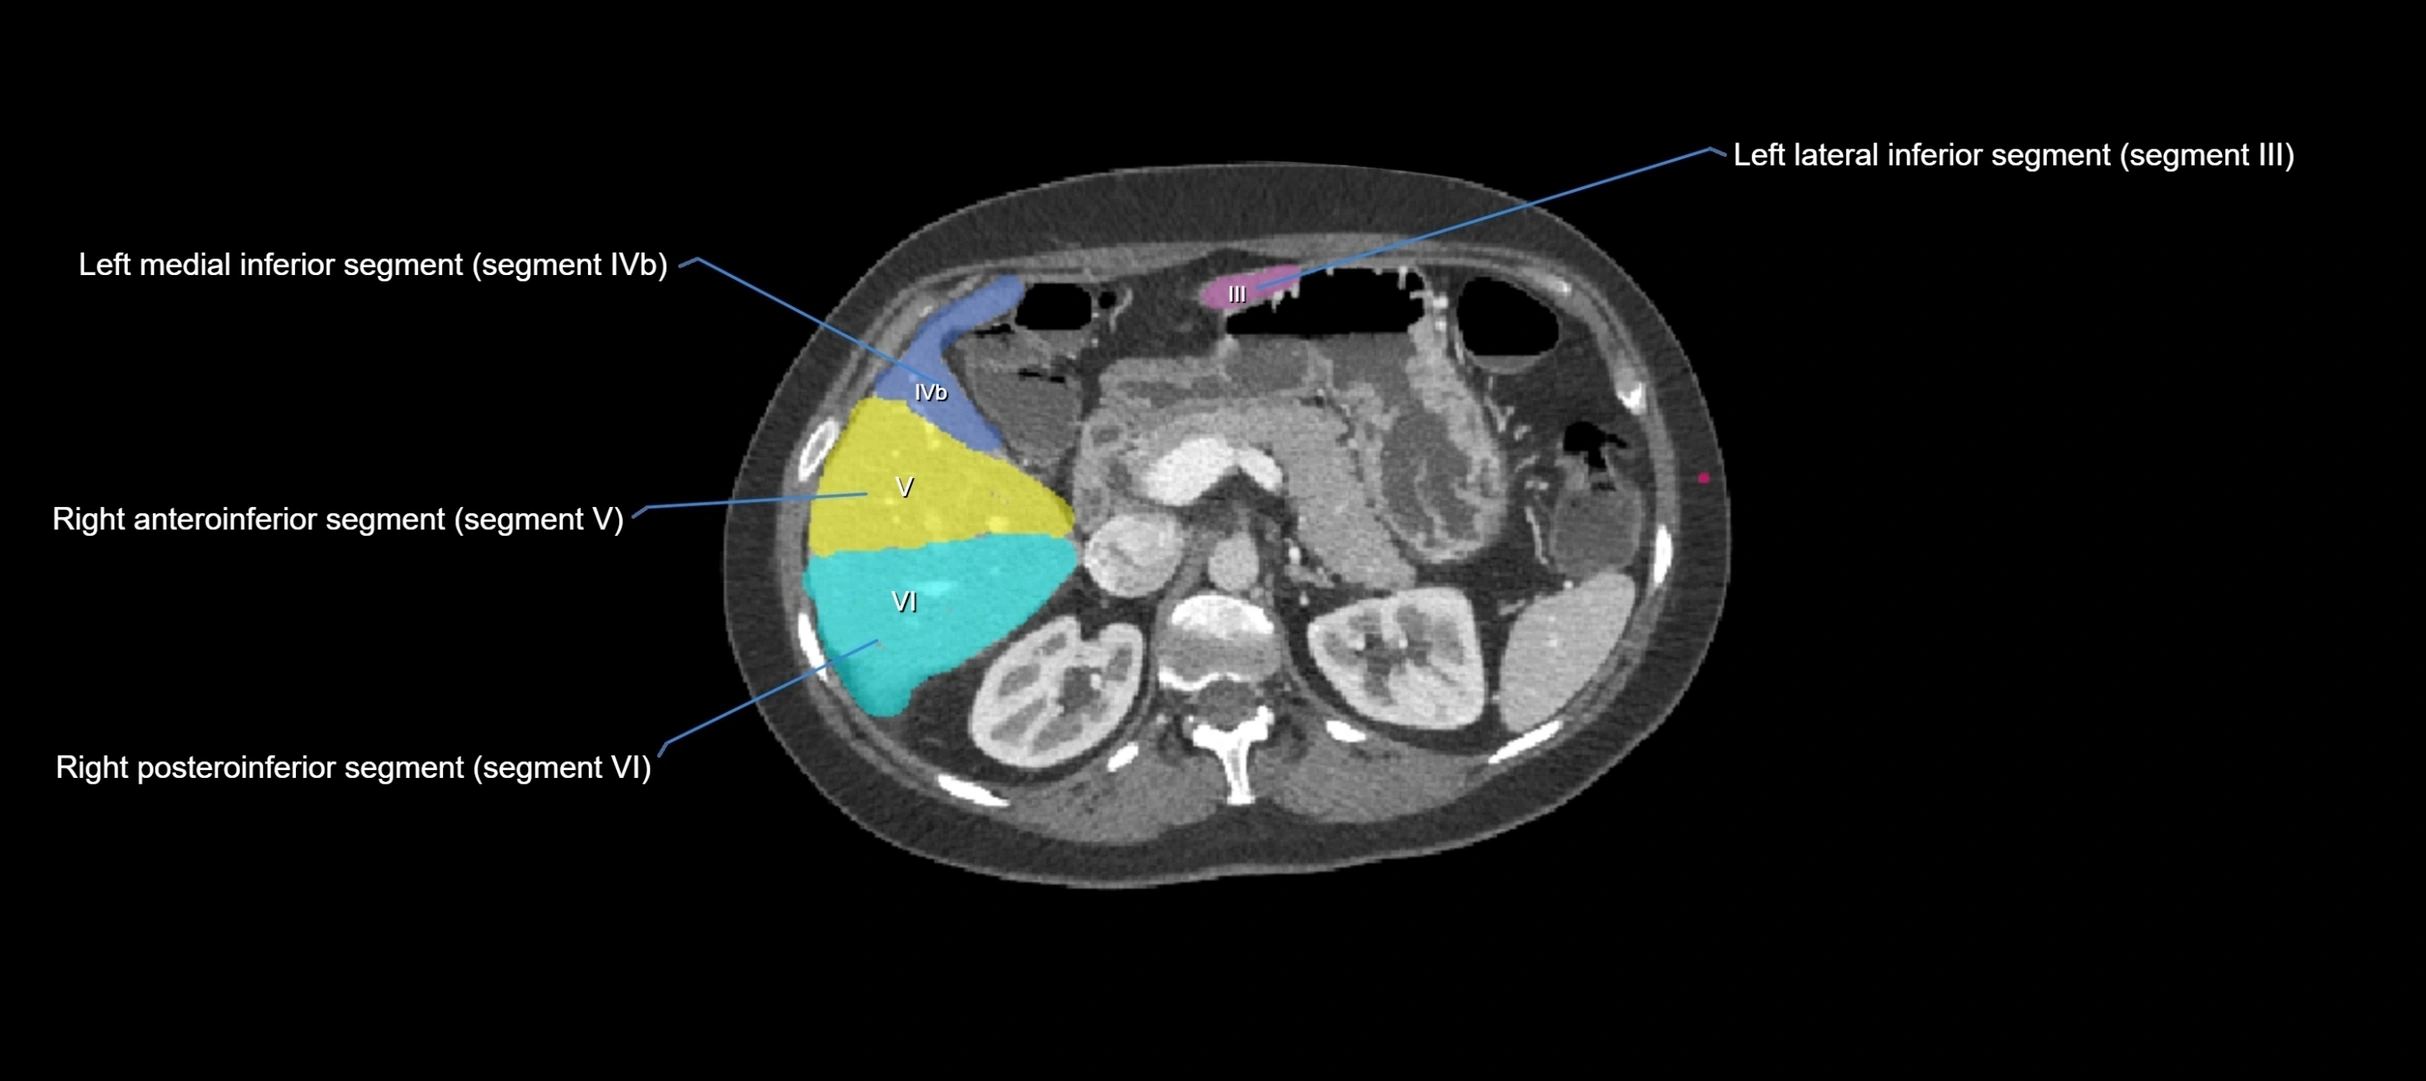

CT Appearance

CT Pre-Contrast:

• Caudate lobe appears as a soft-tissue density, isodense to the rest of the liver

• Enlargement may be appreciated in cirrhosis or Budd–Chiari syndrome

CT Post-Contrast:

• Homogeneous enhancement in the portal venous phase, similar to rest of liver

• Independent venous drainage into the IVC may be visualized

• Lesions follow characteristic CT enhancement patterns (HCC: arterial hyperenhancement with washout; hemangiomas: peripheral nodular enhancement with centripetal fill-in)

CT Venous Phase (functional significance):

• Caudate lobe often enhances relatively more than other lobes in Budd–Chiari syndrome, due to preserved venous outflow

CT Image

image